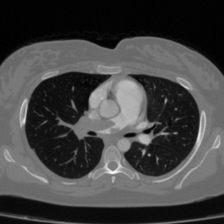

Pulmonary Embolism Detection (FUMPE Dataset): The FUMPE dataset (Ferdowsi University of Mashhad’s Pulmonary Embolism dataset) [21] contains the three-dimensional computed tomography angiography (CTA) scans of 35 patients, amounting to 8792 image slices. Two radiologists manually reviewed all the CTA scans using a semi-automated segmentation method to derive reference labels. In total, the dataset consists of 3,438 PE (pulmonary embolism) annotated regions. Notably, approximately 67% of these regions occur in the peripheral pulmonary arteries, which positions this dataset to be highly advantageous for prototyping and benchmarking sophisticated CAD systems. After a comprehensive review, we completed the collection of CTPA images for 35 patients, totaling 8792 CTPA images, along with updated annotations by the doctors. For performance evaluation, the dataset was divided into an ratio for training and validation. And performance metric were reported on unseen validation samples as suggested in [15].

Table 2 presents a quantitative comparison between the proposed DAUNet and several representative state-of-the-art segmentation models, including CNN-based, transformer-based, and hybrid architectures. The comparison is conducted on the FUMPE dataset using Dice Similarity Coefficient (DSC) and 95th percentile Hausdorff Distance (HD95), together with model parameter count as a measure of computational efficiency.

As shown in Table 2, the proposed DAUNet achieves the best overall segmentation performance, attaining a Dice score of 88.80% and the lowest boundary error with an HD95 of 2.57. These results indicate superior overlap accuracy and more precise boundary delineation compared to all competing methods. In addition, DAUNet maintains a significantly lower model complexity, requiring only 21.07M parameters, which is substantially fewer than several strong baselines.

Notably, models with considerably higher parameter counts, such as SCUNet++ (60.11M), do not achieve comparable segmentation accuracy or boundary robustness on this dataset. Transformer-based and hybrid models, including TransAttUNet and FAT-Net, demonstrate improved performance over classical UNet variants; however, they remain inferior to DAUNet in both DSC and HD95, while requiring higher computational cost.

Overall, these results highlight the effectiveness of the proposed lightweight architecture for pulmonary embolism segmentation. DAUNet consistently delivers superior accuracy and robustness while maintaining a compact model size, making it well suited for deployment in real-time and resource-constrained clinical environments.

Figure 4 and Figure 5 provide visual comparisons of segmentation masks generated by DAUNet and other competing methods on representative samples from both datasets. As illustrated in Figure 4, DAUNet produces more accurate and smoother boundary delineations, closely aligning with the ground truth annotations, even in challenging low-contrast regions or under partial occlusion. A similar performance can be observed in Figure 5, where proposed model accurately identify the pulmonary embolism regions. It is worth nothing that the proposed model achieve best performance in two different imaging modalities, consisting of different sized regions of interest and number of classes demonstrating a good generalization.